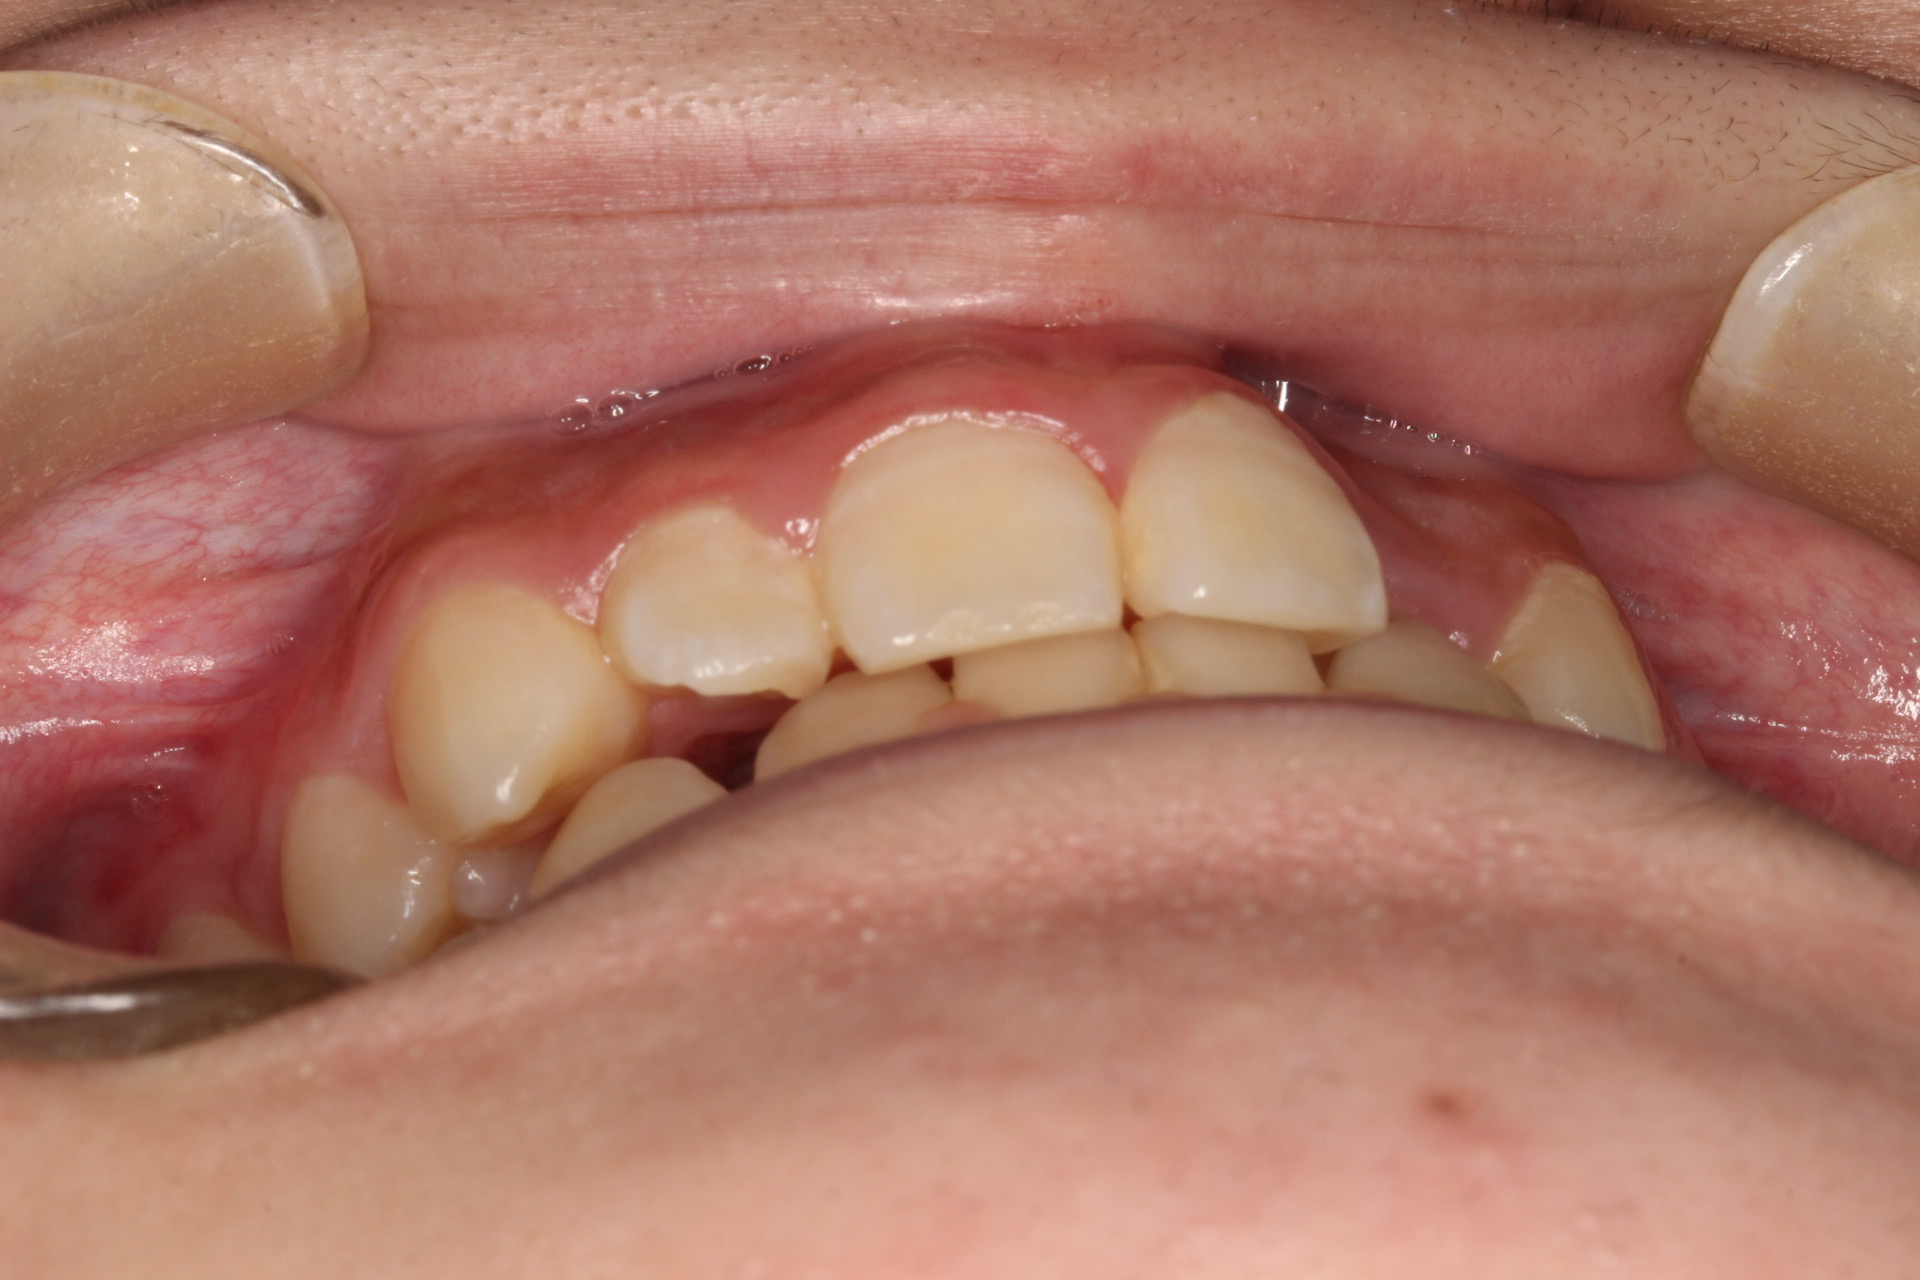

矯正術前:右側

矯正術前:前歯部あおり